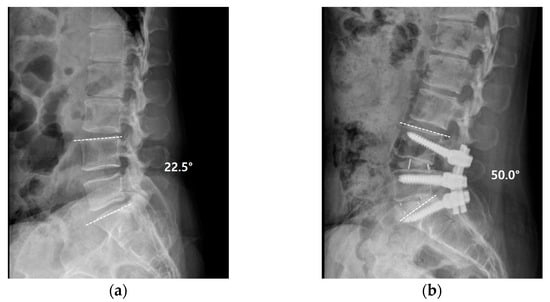

Five days after surgery, she complained of severe pain in her left lower extremity again. Following wound exploration with additional laminectomy, revealing no significant compressive lesion except epidural fibrosis, the symptom improved. Six days after revision surgery, she complained of gradually increasing pain in her left lower extremity, followed by profound weakness (no voluntary movement in the left ankle and big toe dorsiflexion and ankle plantarflexion). Revision surgery revealed severe epidural fibrosis along the thecal sac and L5–S1 roots (left side dominant). Normal dura was identified after peeling the thick epidural fibrosis (Figure 3). Pain and weakness of the left extremity disappeared immediately after surgery. However, two additional surgeries were needed due to the same pain and weakness episodes, several days following the surgeries. Operative findings were also similar to that of the previous surgeries with severe epidural fibrosis around the thecal sac and nerve roots. Symptoms were also alleviated immediately after surgery. Postoperative steroid therapy or narcotics did not work at all. Laboratory and culture studies documented no evidence of infection or rheumatoid disease. Finally, we performed L4–S1 oblique lateral interbody fusion (OLIF) with hyperlordotic cages to ameliorate tethering and traction of the thecal sac and nerve roots through posterior column shortening (Figure 4). Pain and paresthesia were considerably decreased. Weakness was also reduced. Eventually, the patient was able to walk again following six additional surgeries over 11 weeks. After the final surgery, postoperative wound infection by Candida albicans was identified, and treated successfully with antifungal agents. Follow-up MRI at 6 months postoperatively showed a well-decompressed thecal sac and nerve roots. However, roots were clumped and distorted within the thecal sac, suggesting arachnoiditis (Figure 5). Fortunately, her pain in the leg was considerably reduced, without neurological deficits. At the final follow-up, she was doing well with oral medication without taking narcotics (VAS 3) over the 2 years postoperatively.

Figure 4.

(a,b) Lordotic fusion from L4 to S1 with posterior column shortening was conducted to reduce neural tension and stretching of the nerve roots. Lower lumbar lordosis (L4–S1) was increased from 22.5° to 50.0° after surgery.